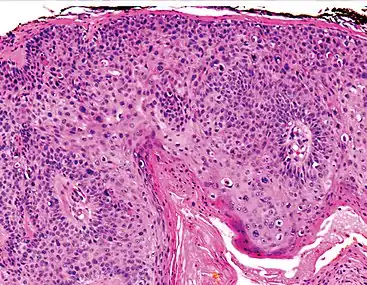

Histopathologically, the epidermis in cSCC in situ (Bowen's disease) will show hyperkeratosis and parakeratosis. There will also be marked acanthosis with elongation and thickening of the rete ridges. These changes will overly keratinocytic cells which are often highly atypical and may in fact have a more unusual appearance than invasive cSCC. The atypia spans the full thickness of the epidermis, with the keratinocytes demonstrating intense mitotic activity, pleomorphism, and greatly enlarged nuclei. They will also show a loss of maturity and polarity, giving the epidermis a disordered or "windblown" appearance.

Two types of multinucleated cells may be seen: the first will present as a multinucleated giant cell, and the second will appear as a dyskeratotic cell engulfed in the cytoplasm of a keratinocyte. Occasionally, cells of the upper epidermis will undergo vacuolization, demonstrating an abundant and strongly eosinophilic cytoplasm. There may be a mild to moderate lymphohistiocytic infiltrate detected in the upper dermis.[12]

In invasive cSCC, tumor cells infiltrate through the basement membrane. The infiltrate can be somewhat difficult to detect in the early stages of invasion: however, additional indicators such as full thickness epidermal atypia and the involvement of hair follicles can be used to facilitate the diagnosis. Later stages of invasion are characterized by the formation of nests of atypical tumor cells in the dermis, often with a corresponding inflammatory infiltrate.[12]